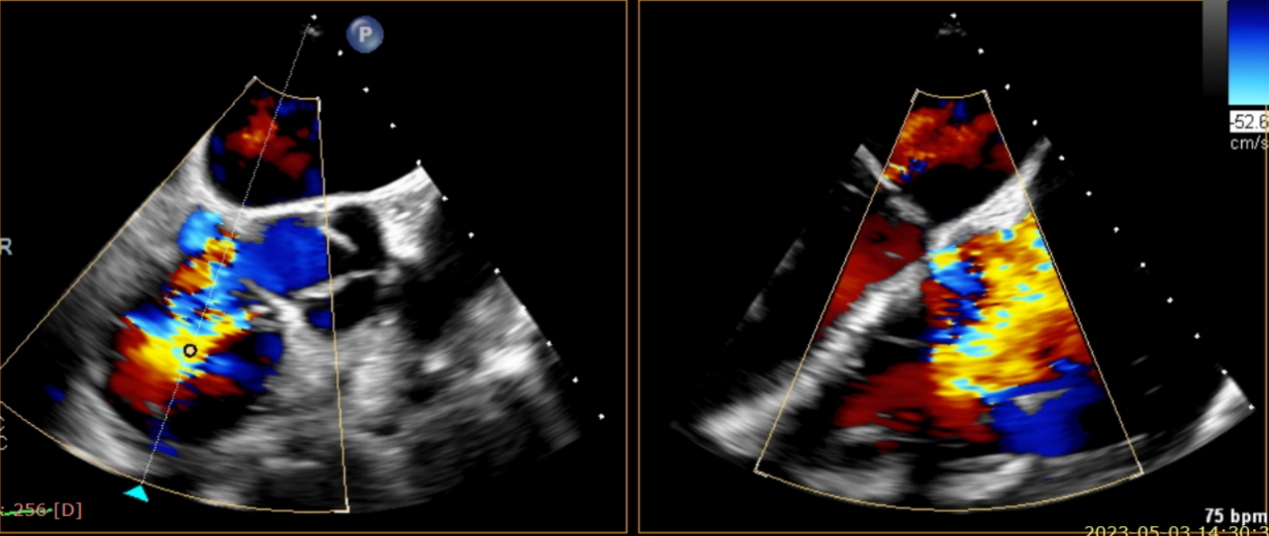

術(shù)前超聲提示大量三尖瓣反流

術(shù)后超聲提示無(wú)瓣周漏